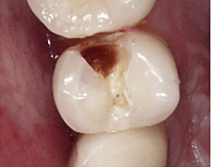

なんと、歯に穴が開いてしまっているのが分かります!

この穴を治すために使う道具を説明して、いざ治療をしていきますが、